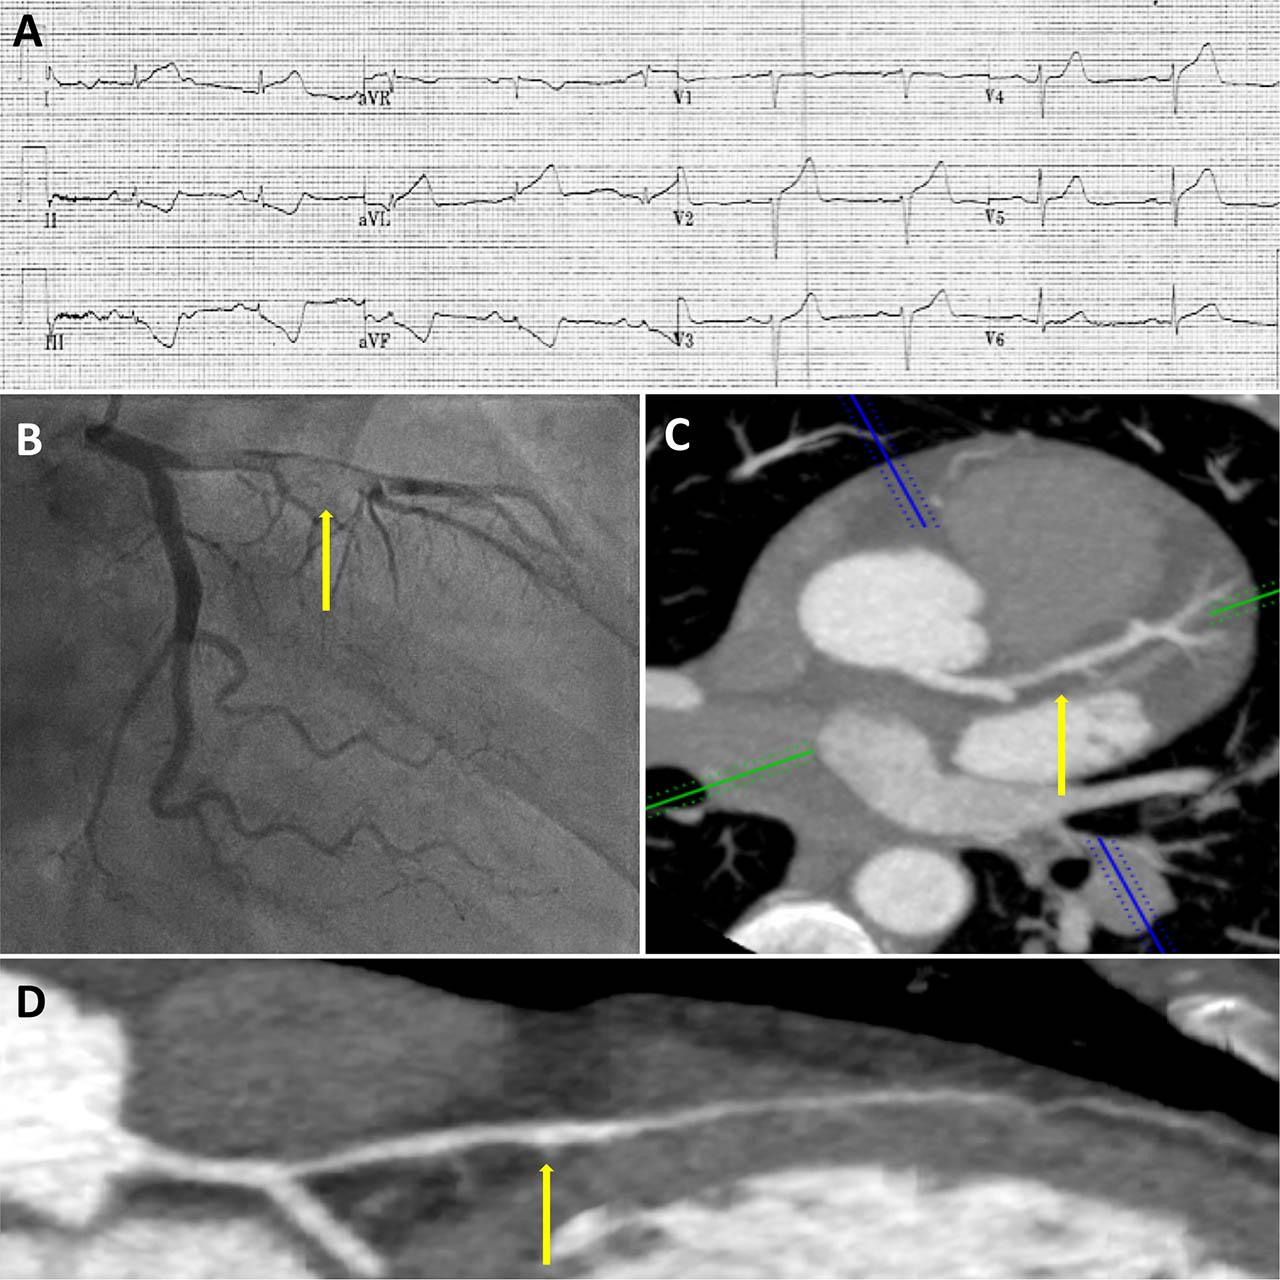

A Electrocardiography showed sinus rhythm with ST-segment elevation in the lateral leads (I and AVL) with reciprocal ST-segment depression in the inferior leads (II, III and AVF). B Coronary angiography was suggestive of coronary artery dissection, with associated thrombus in the left anterior descending (LAD) artery. C, D Computed tomographic coronary angiography (CTCA) showed excellent flow in the LAD with minimal stenosis.

Emergency coronary angiography was suggestive of coronary artery dissection, with associated thrombus in the left anterior descending (LAD) artery (Panel B).

Echocardiography showed mild left ventricular systolic impairment with hypokinesia of the apical anterior, lateral and true apical segments. Computed tomographic coronary angiography (CTCA) 8 days later showed excellent flow in the LAD with minimal stenosis (Panel C, D).